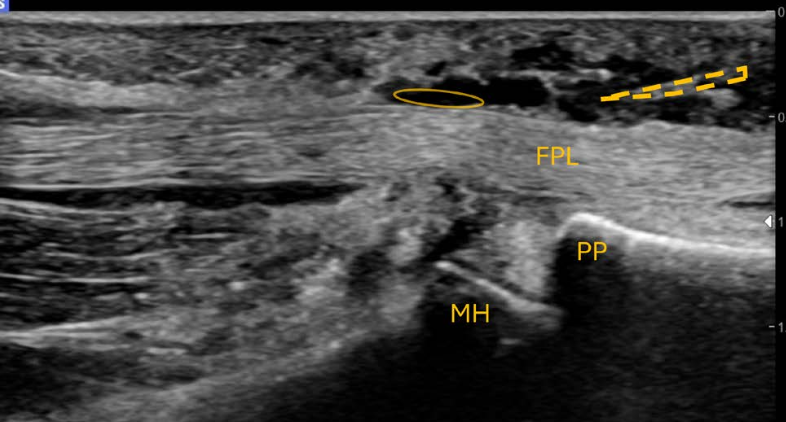

A Novel Ultrasound Assessment Technique of the Ulnar Collateral Ligament to Account for the Valgus Stress Effect of Gravity on the Medial Elbow

Background: The ulnar collateral ligament (UCL) of the elbow is commonly injured in baseball athletes. When assessed in the supine abducted and externally rotated (ABER) position using stress ultrasonography (sUS), even before applying a valgus load, gravity pulls on the forearm, creating an initial valgus load that may distort the resting joint space measurement. Purpose/Hypothesis: The purpose of this study was to measure the valgus stress effect of gravity on the resting joint space and determine if a varus-stressed joint space provides a better baseline measurement. It was hypothesized that there would be a greater resting joint space in the throwing arm in the ABER position as a result of UCL laxity but no difference in joint space under varus stress compared to the nonthrowing arm.